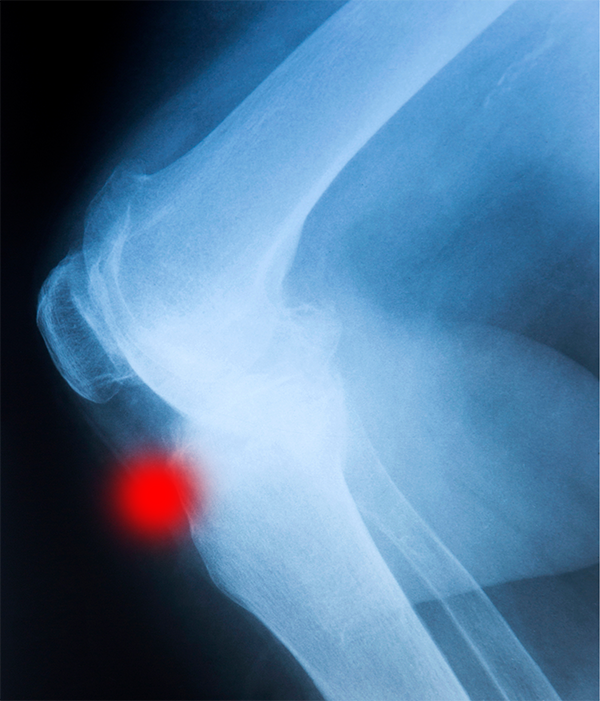

Enfermedad de Osgood Schlatter: qué es, causas, síntomas y tratamiento

La adolescencia es una etapa de cambios físicos y del desarrollo del aparato locomotor, especialmente en jóvenes que practican deporte de forma regular. Por ello,